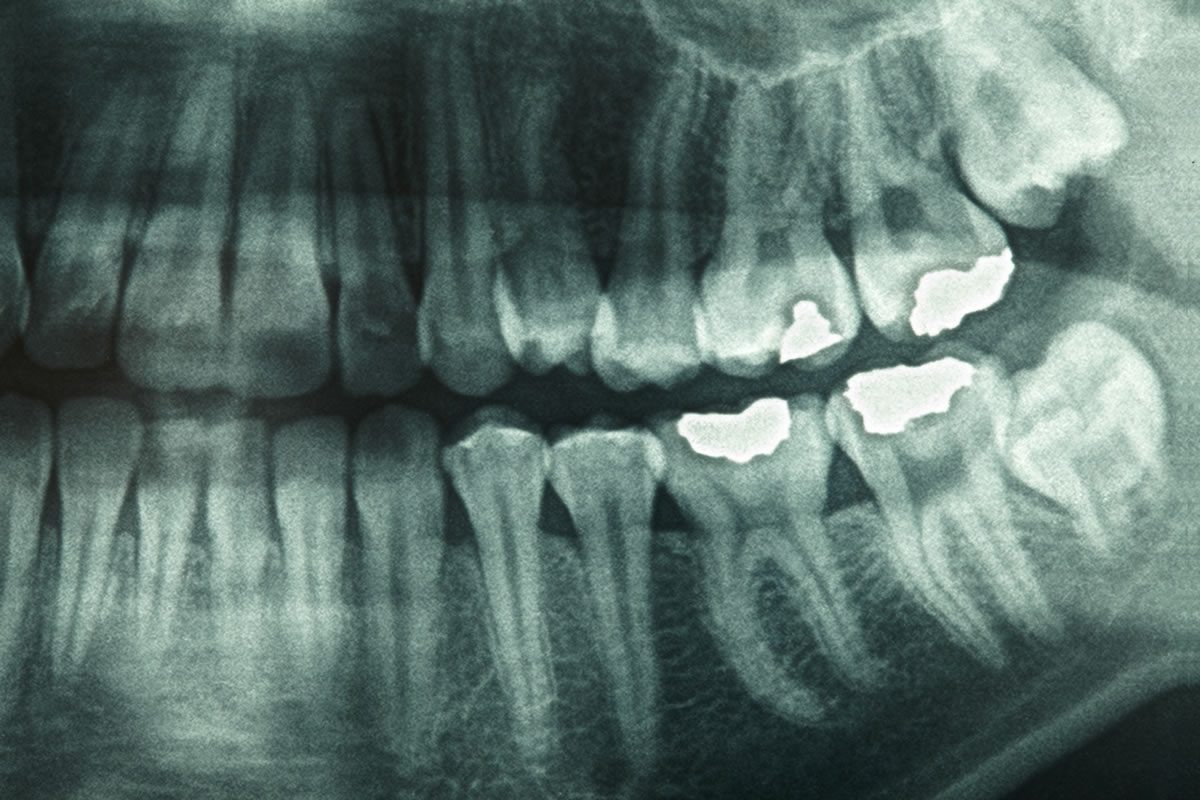

A panoramic X-ray is a two-dimensional image that captures the entire mouth in one shot. Unlike traditional bitewing or periapical X-rays, which focus on small sections of your teeth, panoramic X-rays provide a comprehensive view that includes the upper and lower jaws, temporomandibular joints (TMJs), and even impacted teeth. This makes them particularly useful for treatment planning in orthodontics, implant dentistry, and oral surgery.

Panoramic X-rays can be produced using two types of technology: traditional film and digital imaging. Each method has its advantages, but they also come with different costs and implications for image quality, speed, and patient comfort.

Digital panoramic X-rays use electronic sensors to capture images and display them instantly on a computer screen. These images can be enlarged, enhanced, and adjusted for better diagnostics. On the other hand, film panoramic X-rays require chemical processing, similar to old-fashioned photography, and produce a physical film image that cannot be altered once it's developed.

The clarity and resolution of digital images often surpass that of traditional film, which can result in more accurate diagnoses. Plus, digital files are easier to store, share, and retrieve, making them more convenient for both patients and dental professionals.